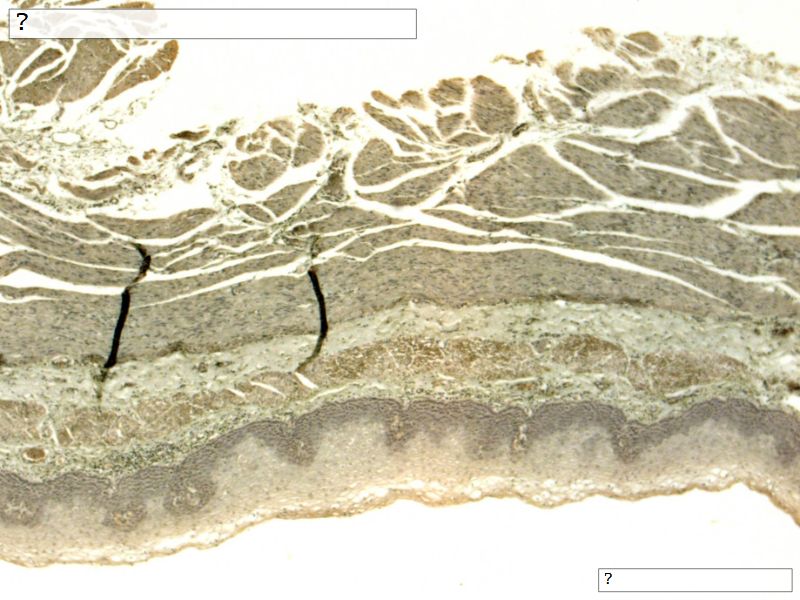

Fill in all the missing labels, and assess as you move through the slides. Answers on the down slide. It is important to do this using pen and paper, and not just glance through the images.